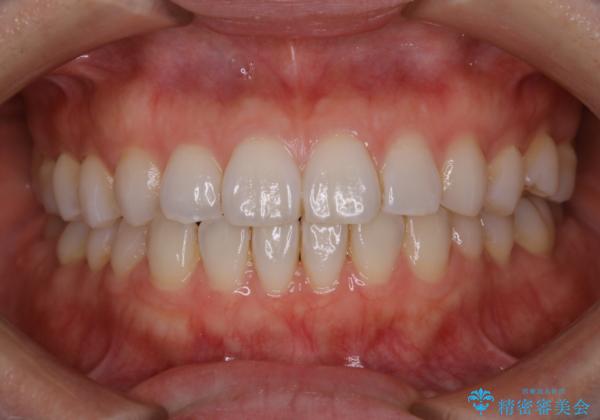

PMTCで見た目を綺麗に

毎日丁寧に歯磨きをしていても、日常生活での飲食物などにより着色してしまうことはあります。PMTCでは、歯の表面の凸凹にミネラルを補給して、ツルツルの表面に仕上げます

歯科医院にて、適切な処置を行うことで、長期的に安定したお口の環境が作られます。まずはカウンセリングなどもおススメです。